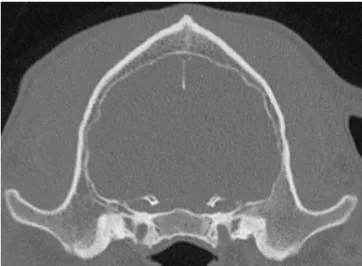

CT image dog unhealthy skull

Unhealthy dog skull

These approaches are under-developed for veterinary patients. Consequently, we have developed a Computed Tomography based approach that allows us to screen dogs for low bone density and have a developed a novel osteodensitometry to objective quantify the density of bones. The bottom figure is a CT image of a dog skull showing that the skull is very thin when compared to a healthy skull on the top.